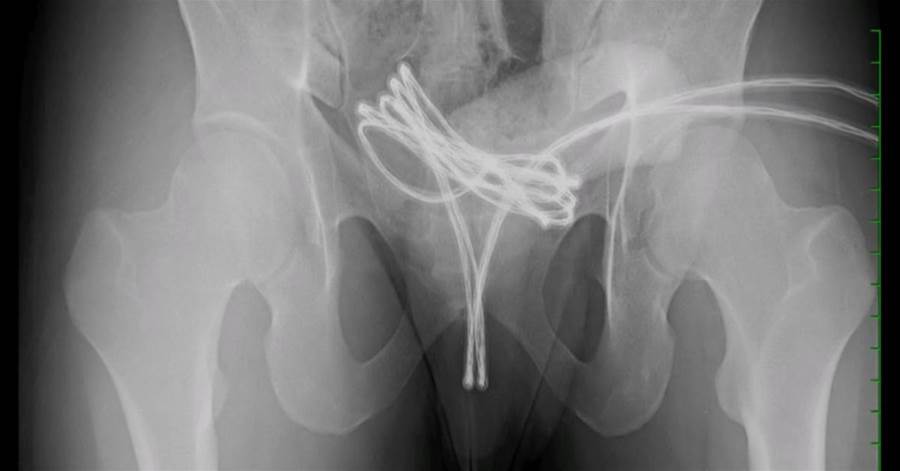

Ao ser encaminhado para avaliação, o paciente hesitou antes de revelar o motivo real de sua visita. Murmurando com vergonha e nervosismo, ele confessou: havia inserido um cabo USB inteiro por seu órgão genital. O objetivo, segundo explicou, era alcançar satisfação sexual — uma prática que, como se descobriu depois, não era inédita para ele.

Exames de imagem revelaram uma situação ainda mais preocupante: o cabo havia sido empurrado até a bexiga, o que tornava qualquer tentativa de remoção sem auxílio médico um risco grave. A complexidade do procedimento exigiu uma cirurgia sob anestesia geral, com auxílio de uma microcâmera para guiar os especialistas durante a delicada extração.